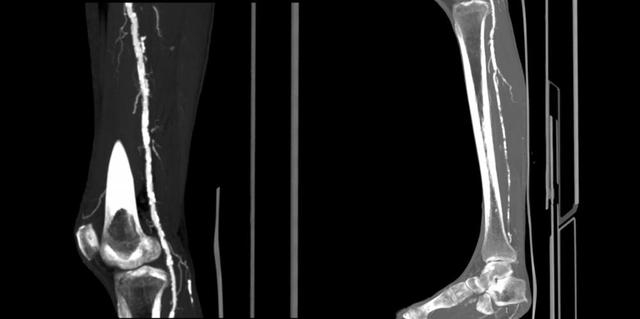

▲球囊扩张术前下肢动脉CTA/图源 重医附二院疼痛科